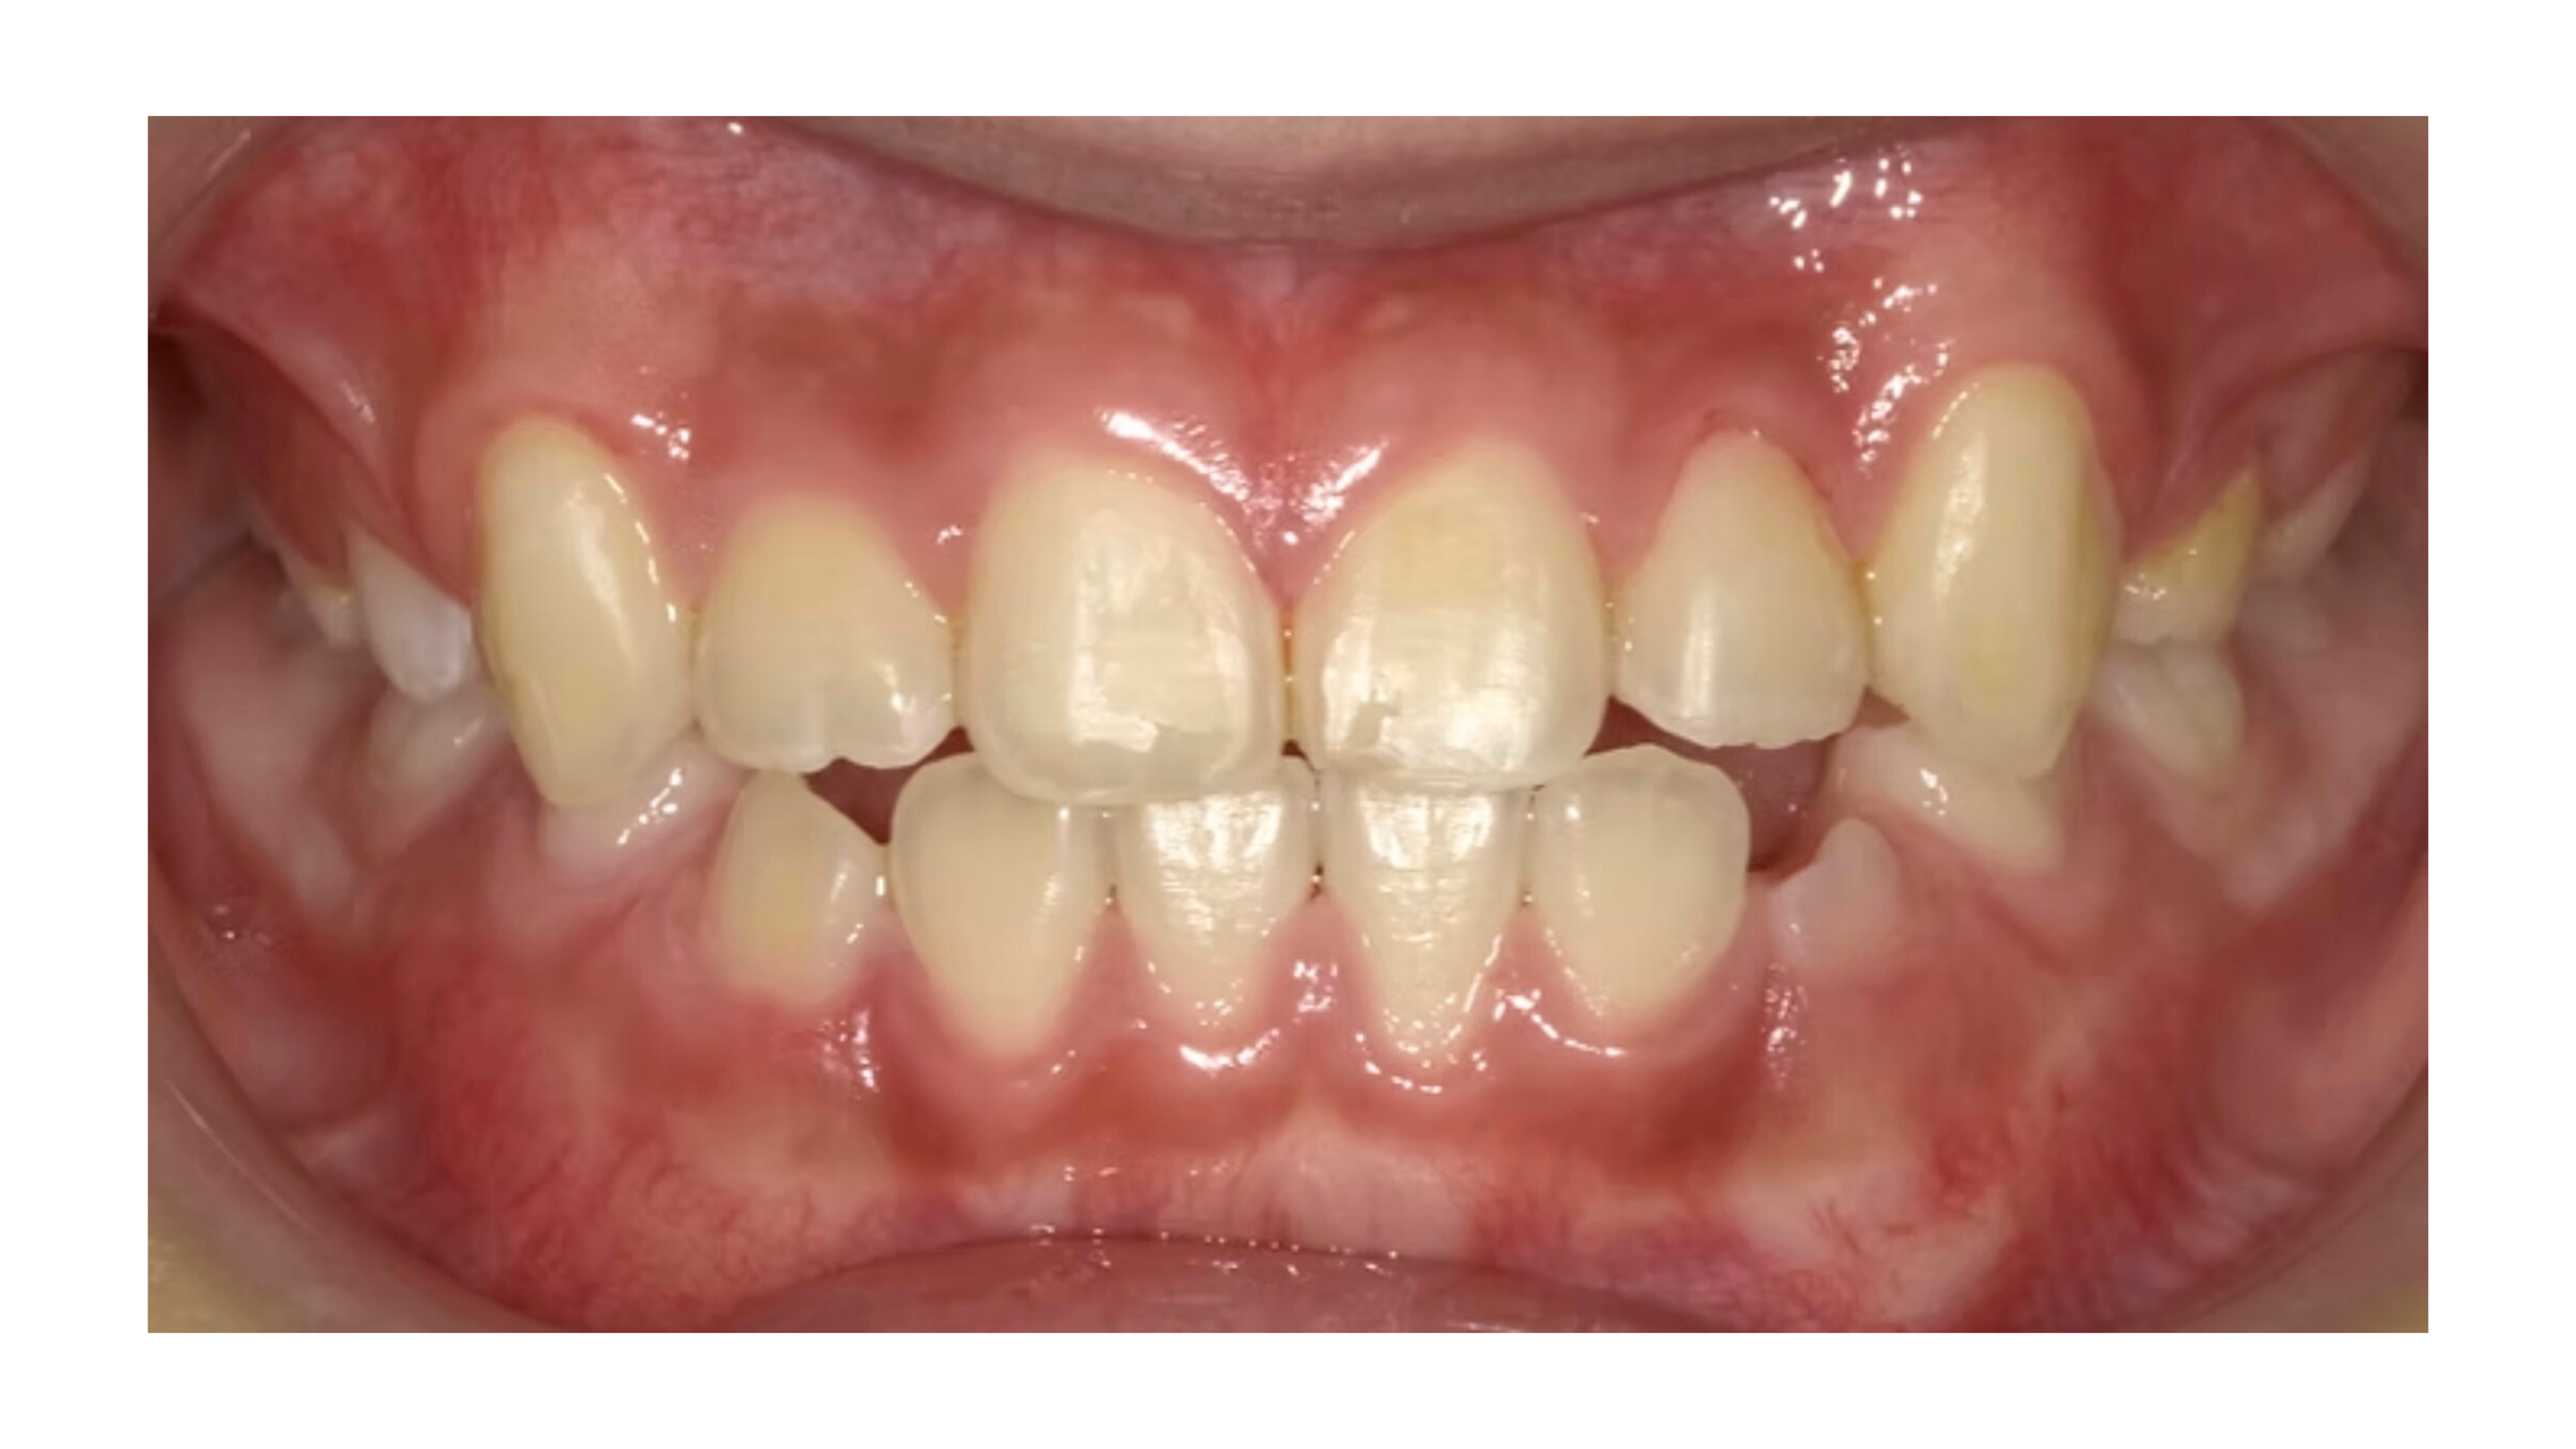

「矯正治療の経過」

小学2年生から矯正治療をスタート。

治療期間は1年6か月でした。

その結果…

反対咬合が改善

上アゴのスペースが確保され、永久歯が並ぶ余裕ができた

前歯の噛み合わせも自然に整い、見た目もすっきり

笑顔もより自然で健康的になりました